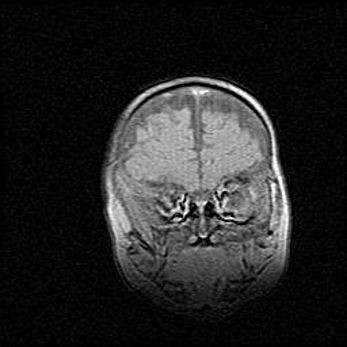

Церебральная ишемия II.

Возраст: 5 дней

Вес: 3400 г

Пол: женский

Окружность головы: 35 см

Срок гестации: 39 недель

Церебральная ишемия – это заболевание, характеризующееся недостаточностью (гипоксией) либо полным прекращением (аноксией) снабжения мозга кислородом по причине закупорки одного или нескольких сосудов. Это приводит к  что метаболическим расстройствам различной степени тяжести в тканях головного мозга, развитию коагуляционных некрозов и гибели нейронов.